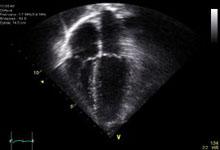

June 15, 2010 – A new study evaluating the safety of an echocardiography contrast agent found that the agent did not have a significant effect on patients’ pulmonary pressures. The findings, concerning the contrast agent Definity Vial For (Perflutren Lipid Microsphere) Injectable Suspension, were presented on June 13 at the American Society of Echocardiography Annual Scientific Sessions in San Diego.

Kevin Wei, M.D., associate professor of medicine at Oregon Health & Science University, presented the data from the phase 4, open-label safety study by Lantheus Medical Imaging Inc. on the effect of Definity on pulmonary and systemic artery hemodynamics in patients with either normal or increased baseline pulmonary artery pressure. The study demonstrated that administration of Definity did not result in any clinically or statistically significant changes in systemic or pulmonary artery hemodynamic measurements in either patient group.